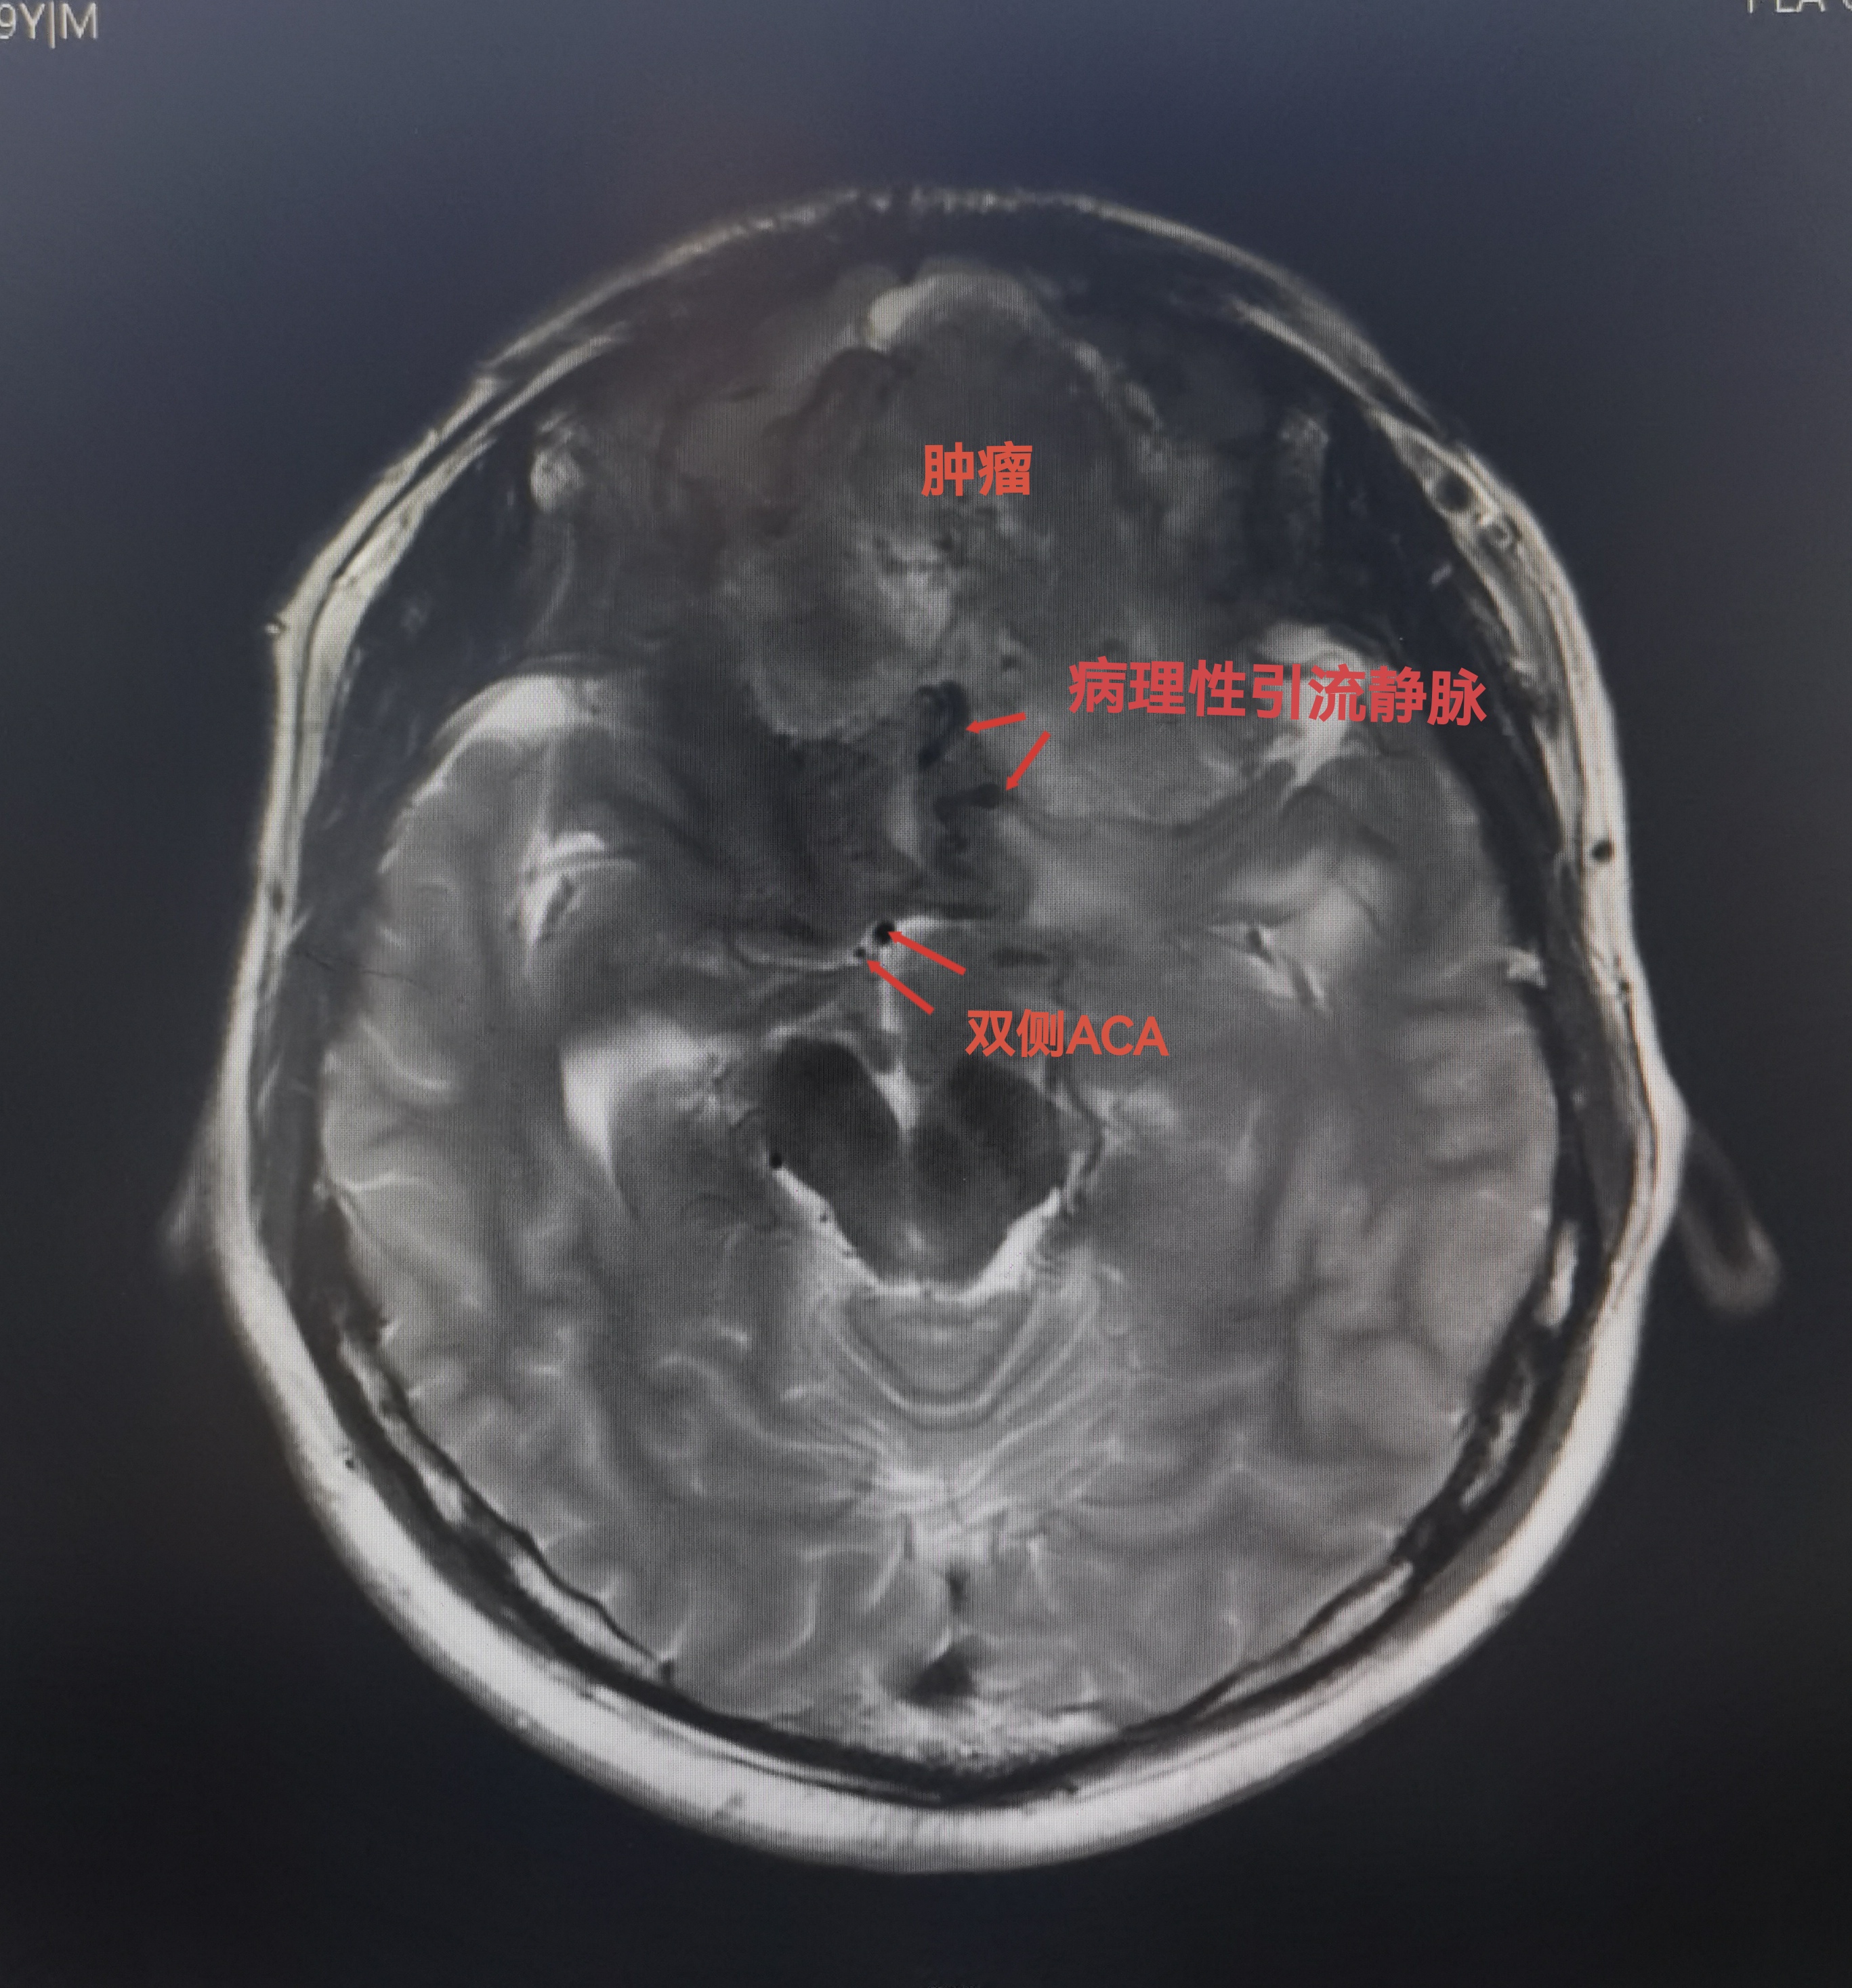

MRI可见肿瘤巨大,中鼻道以上,蝶窦筛窦及双侧额底均为肿瘤组织占据,向两侧到蝶骨嵴。肿瘤分叶状,可明显增强,核心区有坏死。后部可见粗大的静脉。双侧大脑前动脉位于肿瘤的后部。

DSA显示肿瘤多支供血,染色明显。主要来自双侧大脑前及眼动脉(筛前后)和颈外少量供血。因为供血动脉纤细未行栓塞。

注意异常血管,以及双侧大脑前动脉的位置。

造影显示血管移位,肿瘤染色。